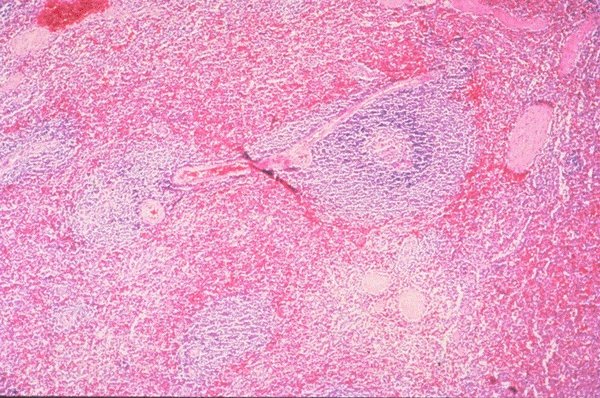

Normal spleen

This is a very low power view of a section of

spleen which has been stained with H&E. The

vascular structures, sinusoids, and intervening

lymphoid areas can be appreciated.